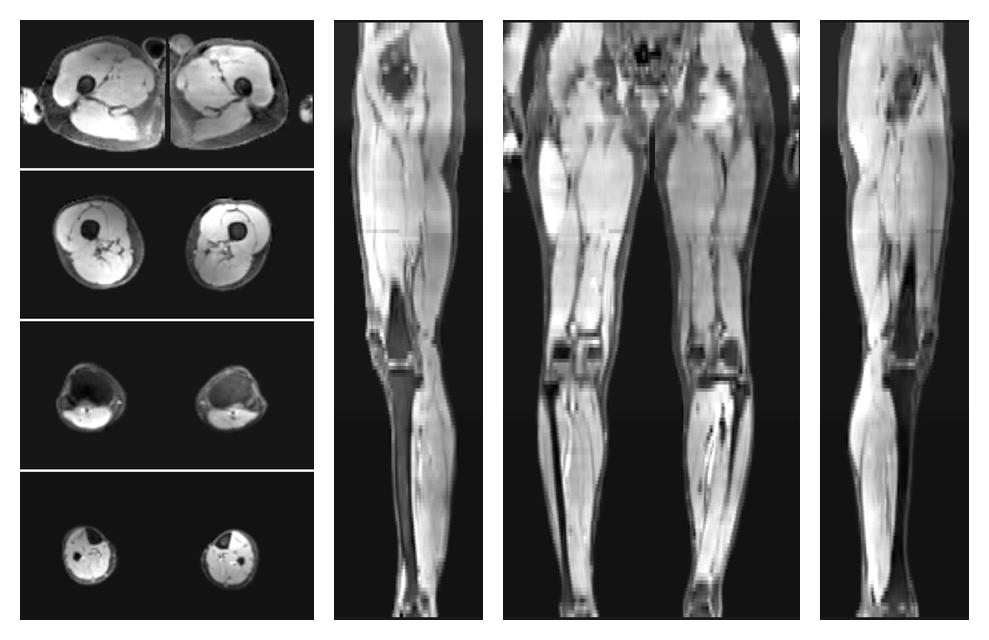

Water only T2 mapping

Multi echo spin echo T2 relaxation time mapping with EPG reconstruction, for information look here».

• Water only signal

The water part of the acquired multi-echo spin echo data.

• Water only T2 relaxation time

The water only T2 relaxation time of the lower extremity obtained from multi echo spin echo t2 mapping with EPG based reconstruction.